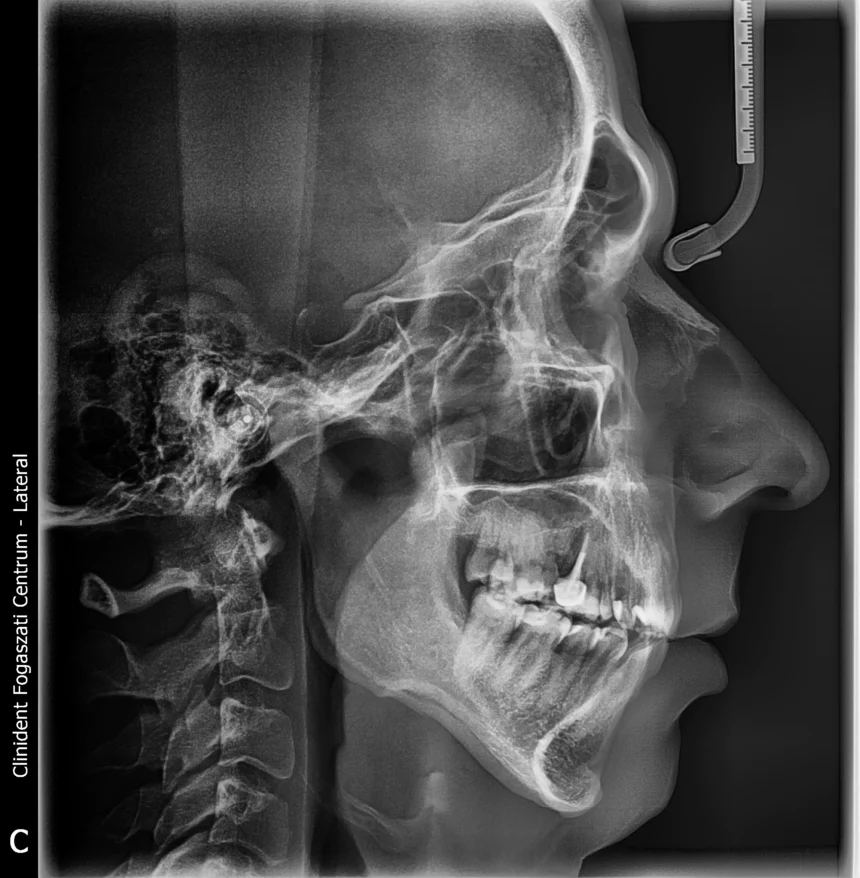

A teleröntgen olyan röntgenfelvétel, amely a teljes arckoponyát mutatja.

Ezt a fogorvosok cephalometrikus röntgenfelvételnek, cephalogramnak is nevezik

Ezt a felvétel típust jellemzően a fogszabályozásban használják a fogszabályozási kezelések tervezésére.

A teleröntgen felvételek tehát extraorális felvételek, melyek a teljes koponyáról – a homloktól a nyaki csigolyáig- adnak képet, azt mutathatják meg kétféle nézetből is. A teleröntgen típusa szerint tehát lehet oldalirányú vagy frontális.

• Oldalirányú teleröntgen felvétel: Az ilyen típusú röntgenfelvétel az arcprofil képét adja vissza, oldalnézetből nyújt képet a koponyáról és az arc szerkezetéről, a fogakról, a fogsor záródásról.